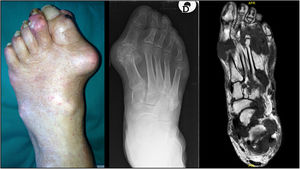

TophiThe presence of tophi in gout indicates chronicity and a lack of effective treatment. They can be found in joints, cartilages, tendons, muscles and periarticular structures.30,31 As stated above, feet are preferred sites for tophi development [Fig. 1], especially in the 1st MTP joints and ankles,27,32 although they may appear in other places of the body such as knees, upper limbs (olecranons, knuckles) or even ears. Presence of tophi in feet has been associated with a decrease in muscle strength32 while some cases of pathological fractures directly related to tophi have been described.33